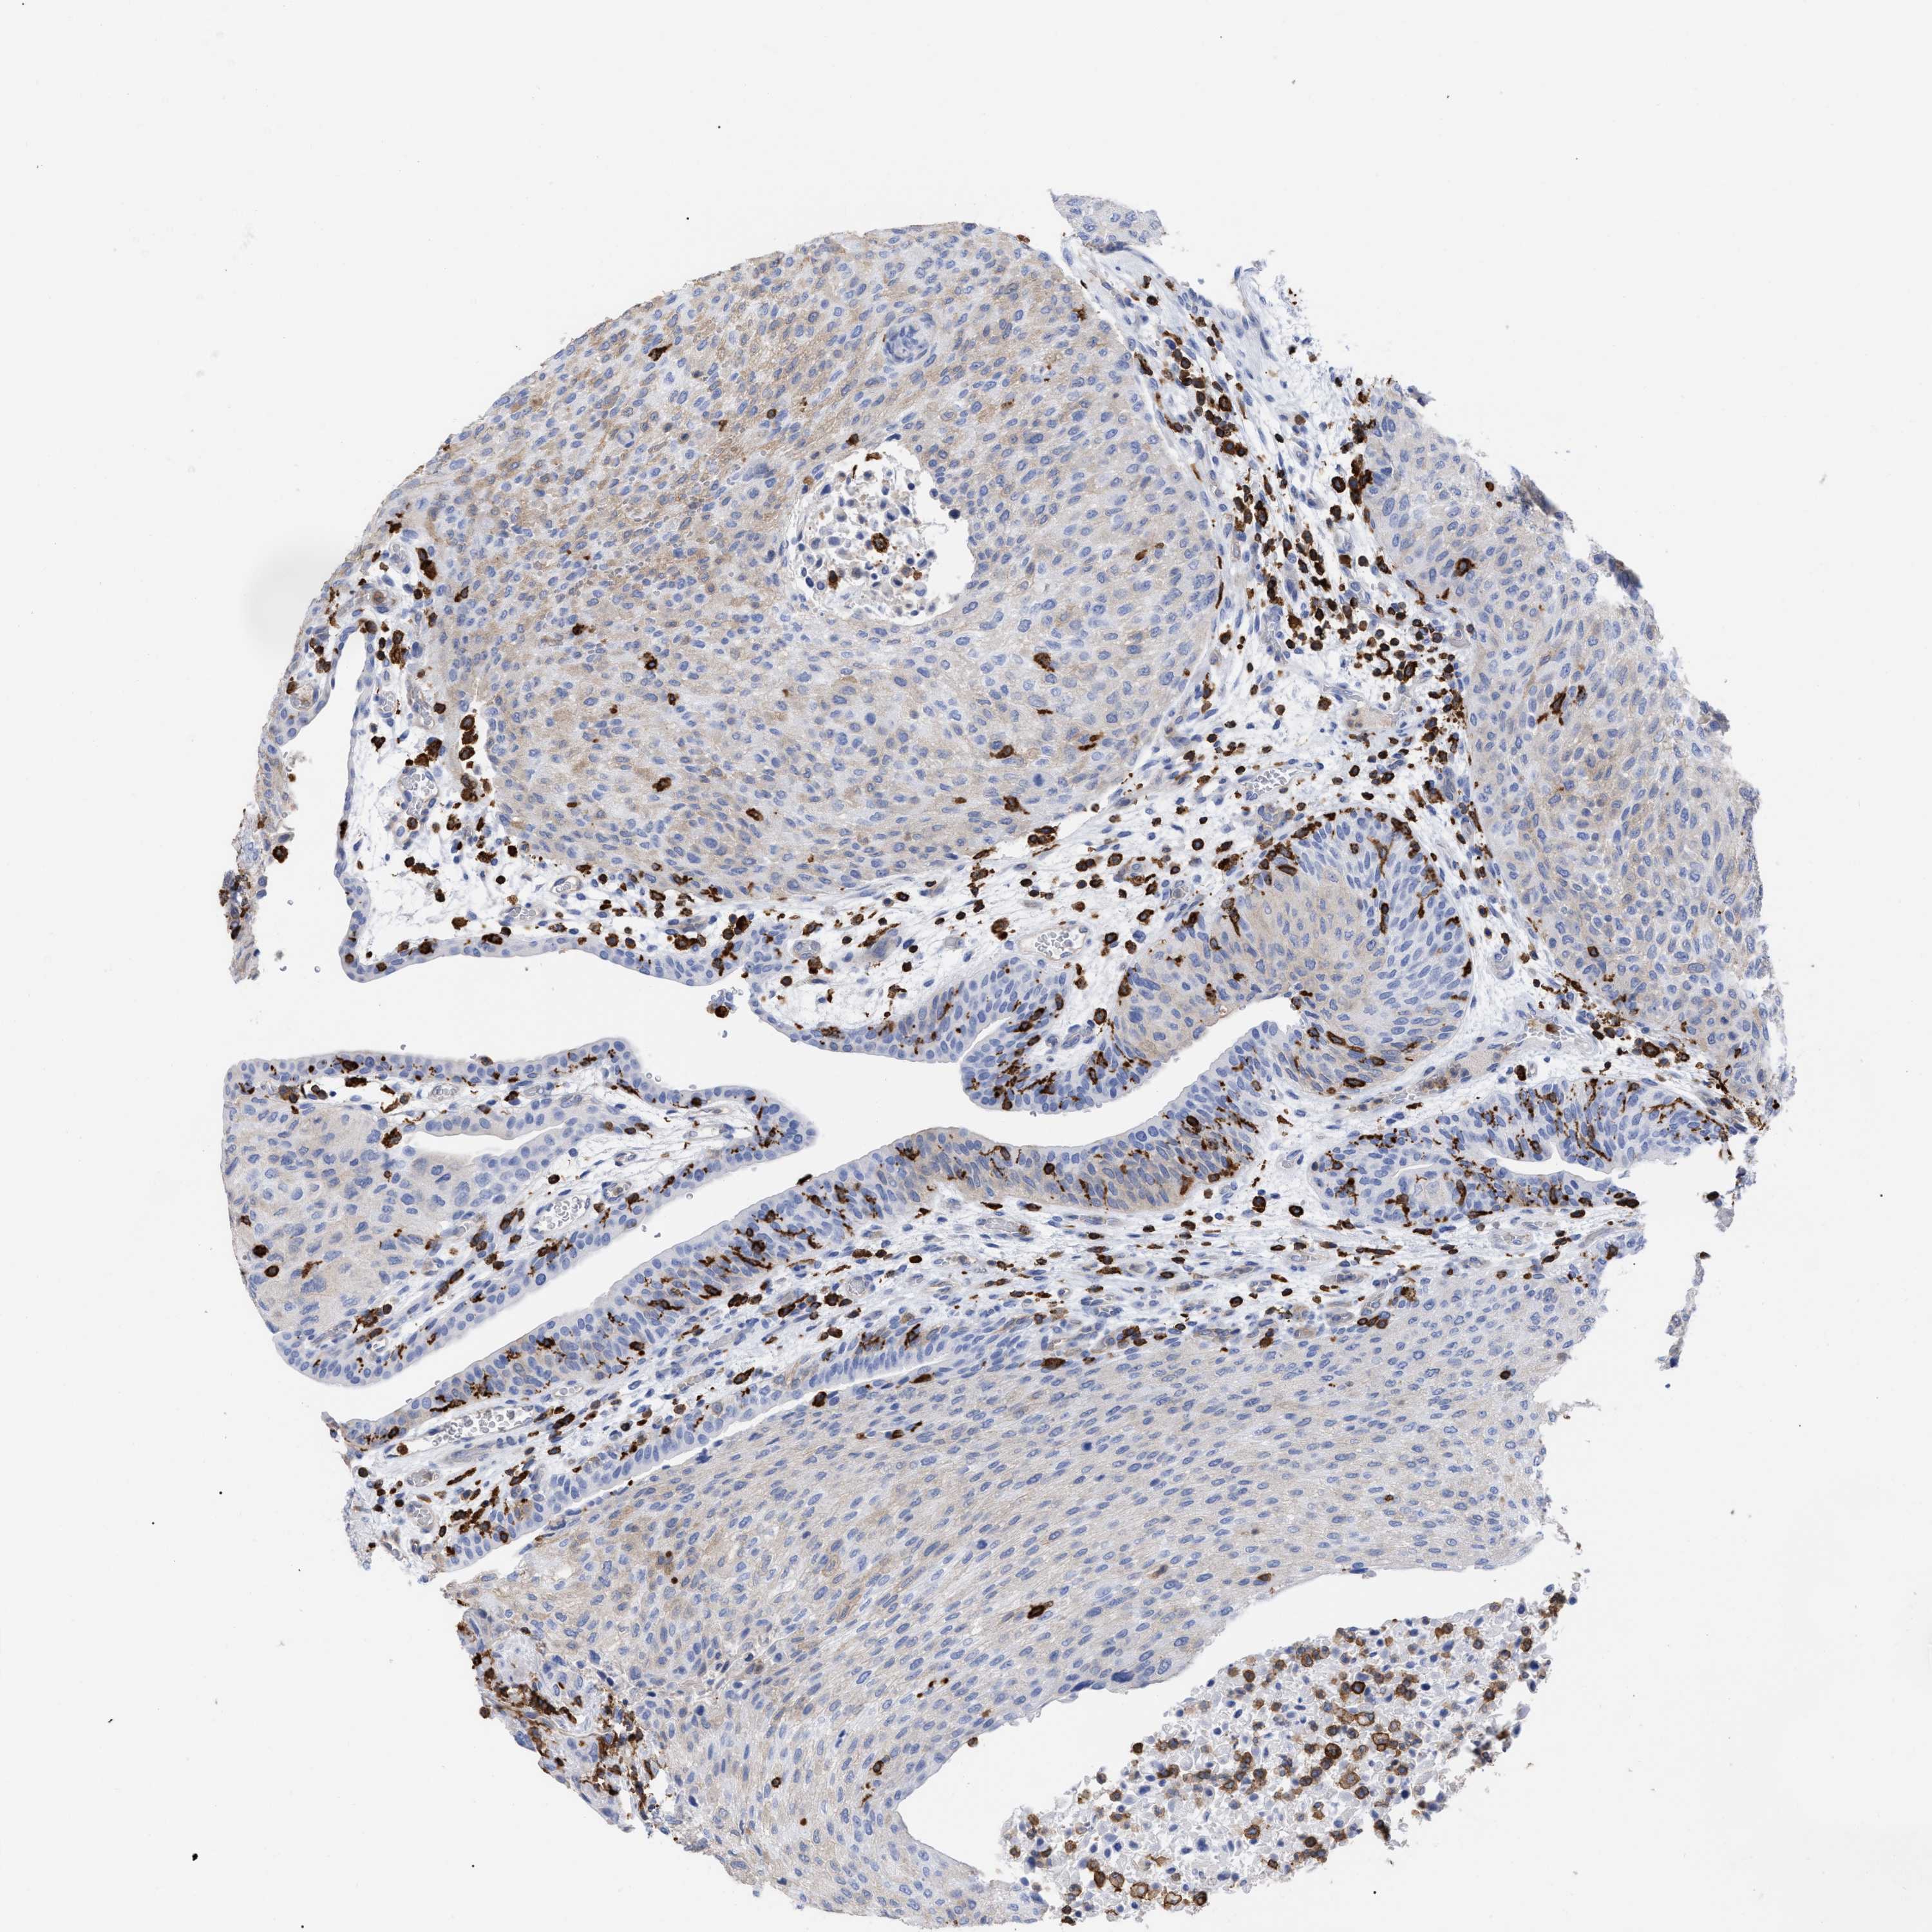

UROTHELIAL CANCER - Protein expressioni

A mouse-over function shows sample information and annotation data. Click on an image to view it in a full screen mode. Samples can be filtered based on level of antibody staining by selecting one or several of the following categories: high, medium, low and not detected. The assay and annotation is described here.

Antibody stainingi

Antibody staining in the annotated cell types in the current human tissue is reported as not detected, low, medium, or high, based on conventional immunohistochemistry profiling in selected tissues. This score is based on the combination of the staining intensity and fraction of stained cells.

Each image is clickable and will lead to virtual microscopy that enables deeper exploration of all samples and also displays staining intensity scores, fraction scores and subcellular localization as well as patient and tissue information for each sample.

Antibody HPA019143

Staining

High

Medium

Low

Not detected

Intensity

Strong

Moderate

Weak

Negative

Quantity

>75%

75%-25%

<25%

None

Location

Nuclear

Cytoplasmic/membranous

Cytoplasmic/membranous,nuclear

Urothelial carcinoma, Low grade

Urothelial carcinoma, High grade